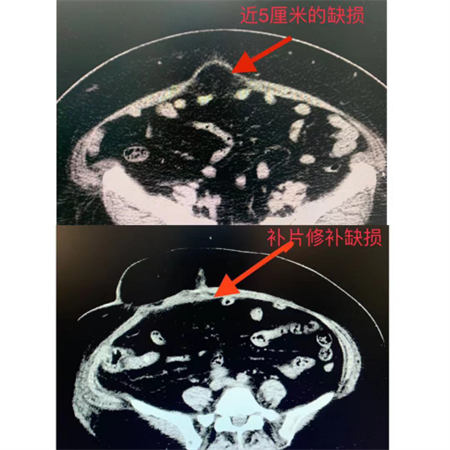

经检查,陆阿姨在脐部包块出现初期,缺损较小,但后来因腹腔脏器反复突出,加之肥胖,局部压力大,导致缺损越来越大,突出的东西就越来越多,回不去,卡住了并引起疼痛症状。手术一是需要把突出的腹腔内容物放回去,缝合缺损;二是因缺损大,为防止术后脐疝复发,还要放置补片加强肚脐处强度。

胃肠外科在完善相关检查,估患者心肺功能可耐受手术后,制定了精细手术方案,齐力为陆阿姨顺利实施了腹腔镜下脐疝补片修补手术,术后陆阿姨康复顺利,已于近日出院。

据悉,本次利用腹腔镜进行的脐疝补片修补术,是医院的首例。胃肠外科表示,脐疝发病率比较低,但成人脐疝绝大多数需要手术缝合,对于缺损大的,还要放置补片。胃肠外科针对病人疝的类型、大小及病人情况,为病人制定个体化的手术方案,这例腹腔镜脐疝补片修补术的顺利完成,也体现了玉溪市人民医院胃肠外科在处理腹壁疝方面又取得了一个新的成绩。(胃肠外科/金杰波) |